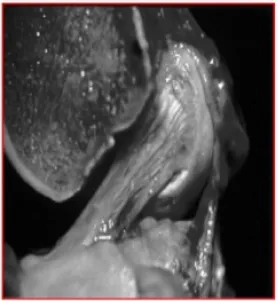

image

Fig. 1. Sagital view of cadaver knee showing anteromedial and posterolateral bundle of ACL. ACL runs from medial aspect of lateral femoral condyle to tibial spine.